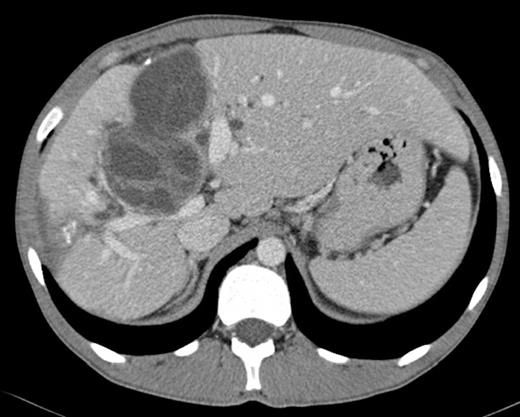

Surgical exploration confirmed the numerous peritoneal hydatid cysts and identified more lesions in the larger omentum (ranging from 3-12 cm) (Fig. 3). They were all resected, and a splenectomy was performed to remove completely the hilum cyst (Fig.4). Hydatid disease of the liver was massive, except in segments 1, 2 and 3. A cyst developing in segment 7 (7 cm) invaded the diaphragm and another voluminous cyst of 12 cm occupied the entire segment 8. A cyst of 8 cm in segments 4 and 5 involved the hepatic confluence, with destruction of the right hepatic duct and promoting a major biliary fistula with the left hepatic duct, confirmed by intra-operative transcystic cholangiography. The left hepatic duct near the hilar plate was included in the pericystic wall near segment 3. This cyst was chemically inactivated using iodopovidone (20 minutes), evacuated and followed by a thorough exploration of the cavity, which showed multiple biliary fistulae from the right sectorial hepatic ducts and a large defect in the left hepatic duct (Fig. 5). An extended right hepatectomy (segments 4 – 8), partial resection of the diaphragm and partial resection of the left hepatic duct including the fistula was performed. Reconstruction of biliary continuity was assured by a hepaticocholedocostomy, over a T-tube (Fig. 6). Confirmation of sectorial left hepatic ducts patency was done by intra-operative cholangiography.

Hepatic hydatid cyst in segments 4 and 5, after inactivation and evacuation, involving the hepatic confluence, with total destruction of the right hepatic duct and fistula formation to the left hepatic duct.